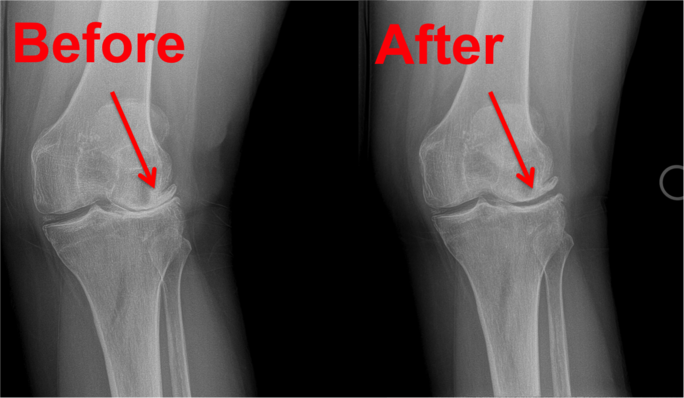

Knee Pain Sufferers are now finding relief with treatments from:

✅Chronic Knee Pain

✅Osteoarthritis

✅Knee Degeneration

The Newest Knee Pain Solution is now available locally and can effectively reduce and even eliminate your pain without surgery or addictive medications.